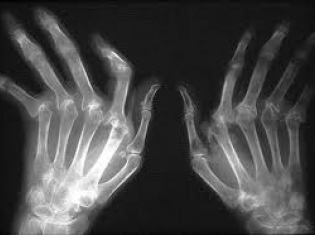

Reumofan Plus is labeled in Spanish and promoted for treating arthritis, muscle pain, osteoporosis, bone cancer, and other conditions.